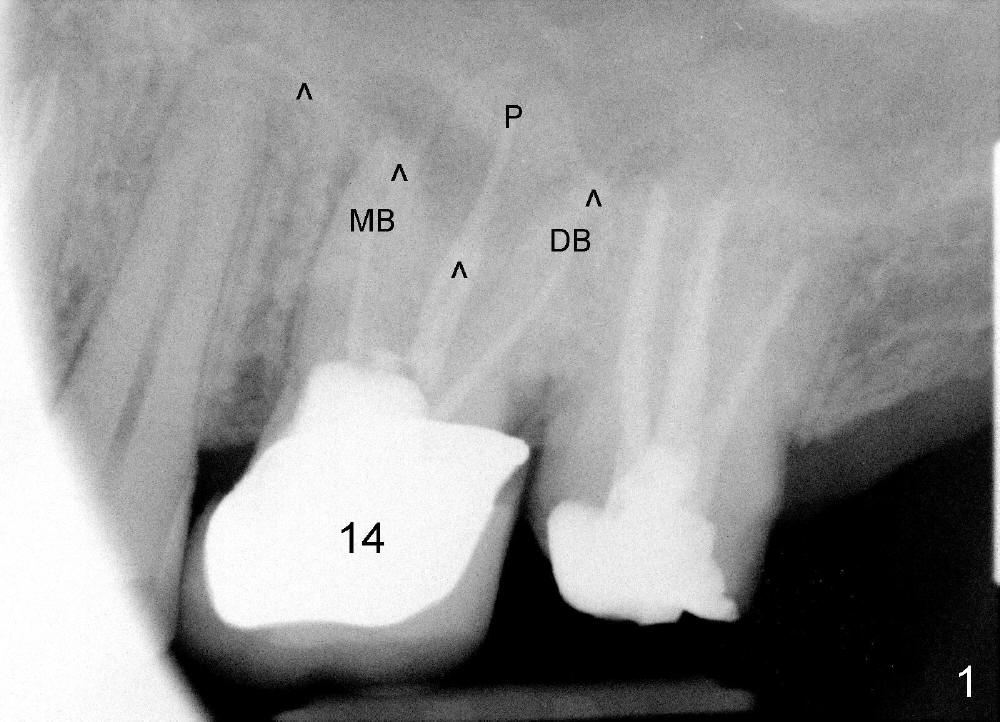

A 49-year-old man has multiple restoration (Fig.1). The tooth #14 appears to be non salvageable (Fig.2-6). The most interesting observation is that the sinus floor (Fig.1 ^) appears to be coronal to the tips of all three roots (mesiobuccal (MB), distobuccal (DB) and palatal (P)). This anatomic feature is confirmed by CBCT study (Fig.2). It will increase insertion torque of an implant to be placed if the sinus floor is raised among the root tips. That is, the apical portion of a large implant is engaged to the area among the apical portion of the three sockets. Let us use Fig.2 Coronal section for design of immediate implant with sinus lift. Click each figure for narrative.